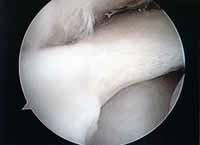

第2段階軟骨形成術

軟骨の剥離や亀裂が①より少し進んだ段階です。放っておくとさらに軟骨欠損が進み軟骨障害は広くなり且つ深くなります。この段階ではまだドリリングなどの操作は不要です。第3段階軟骨障害との間は幅広く関節鏡で見てみないと最終的に判断できません。この段階では手術結果は比較的よく平均75~90点ほどになります。